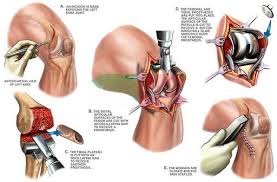

Advanced surgical techniques, including minimally invasive and robotic-assisted procedures, improve precision, reduce tissue damage, and shorten recovery time. These features ensure that patients regain mobility faster, prevent complications, and achieve long-term joint stability.

During government approved joint surgery, surgeons use advanced techniques, including robotic assistance and minimally invasive approaches. These methods reduce tissue trauma, blood loss, and post-operative pain while ensuring accurate implant placement and proper joint alignment.

Patients benefit from smaller incisions, faster recovery, and shorter hospital stays. Precise surgery restores joint function, improves stability, and ensures long-term durability. Advanced surgical execution also minimizes complications and improves overall patient satisfaction.